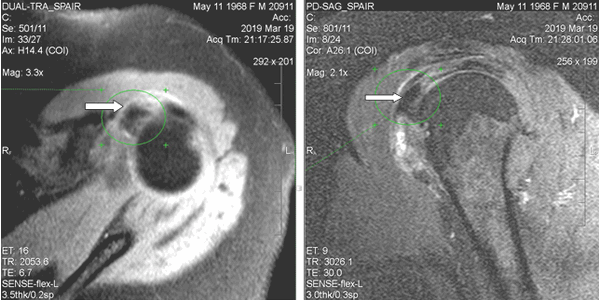

При магнитно-резонансной томографии (март 2019 г.) выявлены неравномерный отек капсулы, неоднородная оссификация капсулы в медиальном отделе. В полости сустава физиологическое количество жидкости. В субдельтовидно-субакромиальной сумке небольшое количество выпота (толщиной до 0,2 см). Суставная щель равномерная, признаков подвывиха головки плечевой кости не выявлено. Краевые заострения суставной впадины лопатки. Акромиально-плечевой промежуток 0,7 см (достаточный). Умеренный отек околосуставных мягких тканей. Ротаторная манжета: сухожилие надостной мышцы с явлениями слабого отека, целостность сохранена; сухожилие подлопаточной мышцы с явлениями слабого отека и дегенеративных изменений; целостность остальных сухожилий (подостной, малой круглой мышц) не нарушена, структура сухожилий не изменена. По сравнению с МР исследованием от января 2018 г. отмечаются более раздробленная и обширная оссификация в медиальном отделе капсулы и субдельтовидной сумки; усиление отека околосуставных мягких тканей; основной кальцинат сместился кверху, под сухожилие надостной мышцы (ранее находился чуть дистальнее сухожилия подлопаточной мышцы) (рис. 2).

Рис. 2. МР-томограммы левого плечевого сустава пациентки Л., 50 лет (март 2019 г.). Определяется утолщение стенок субдельтовидной сумки, крупный кальцинат на 10-11 часах условного циферблата головки плечевой кости (обозначен стрелками), под сухожилием надостной мышцы. Обращают на себя внимание нечеткость контуров кальцината и перифокальный отек мягких тканей, что характерно для фазы резорбции и соответствует клинической картине

Таким образом, магнитно-резонансная томография, выполненная с интервалом 1 год и 2 месяца, позволила наблюдать за динамикой патологических изменений в плечевом суставе, определить фрагментацию и частичную резорбцию ранее выявленного основного крупного кальцината с его «перемещением» в зоне медиального отдела капсулы и субдельтовидной сумки, наглядно продемонстрировала радиологические отличия фаз покоя и резорбции оссифицирующего капсулита.